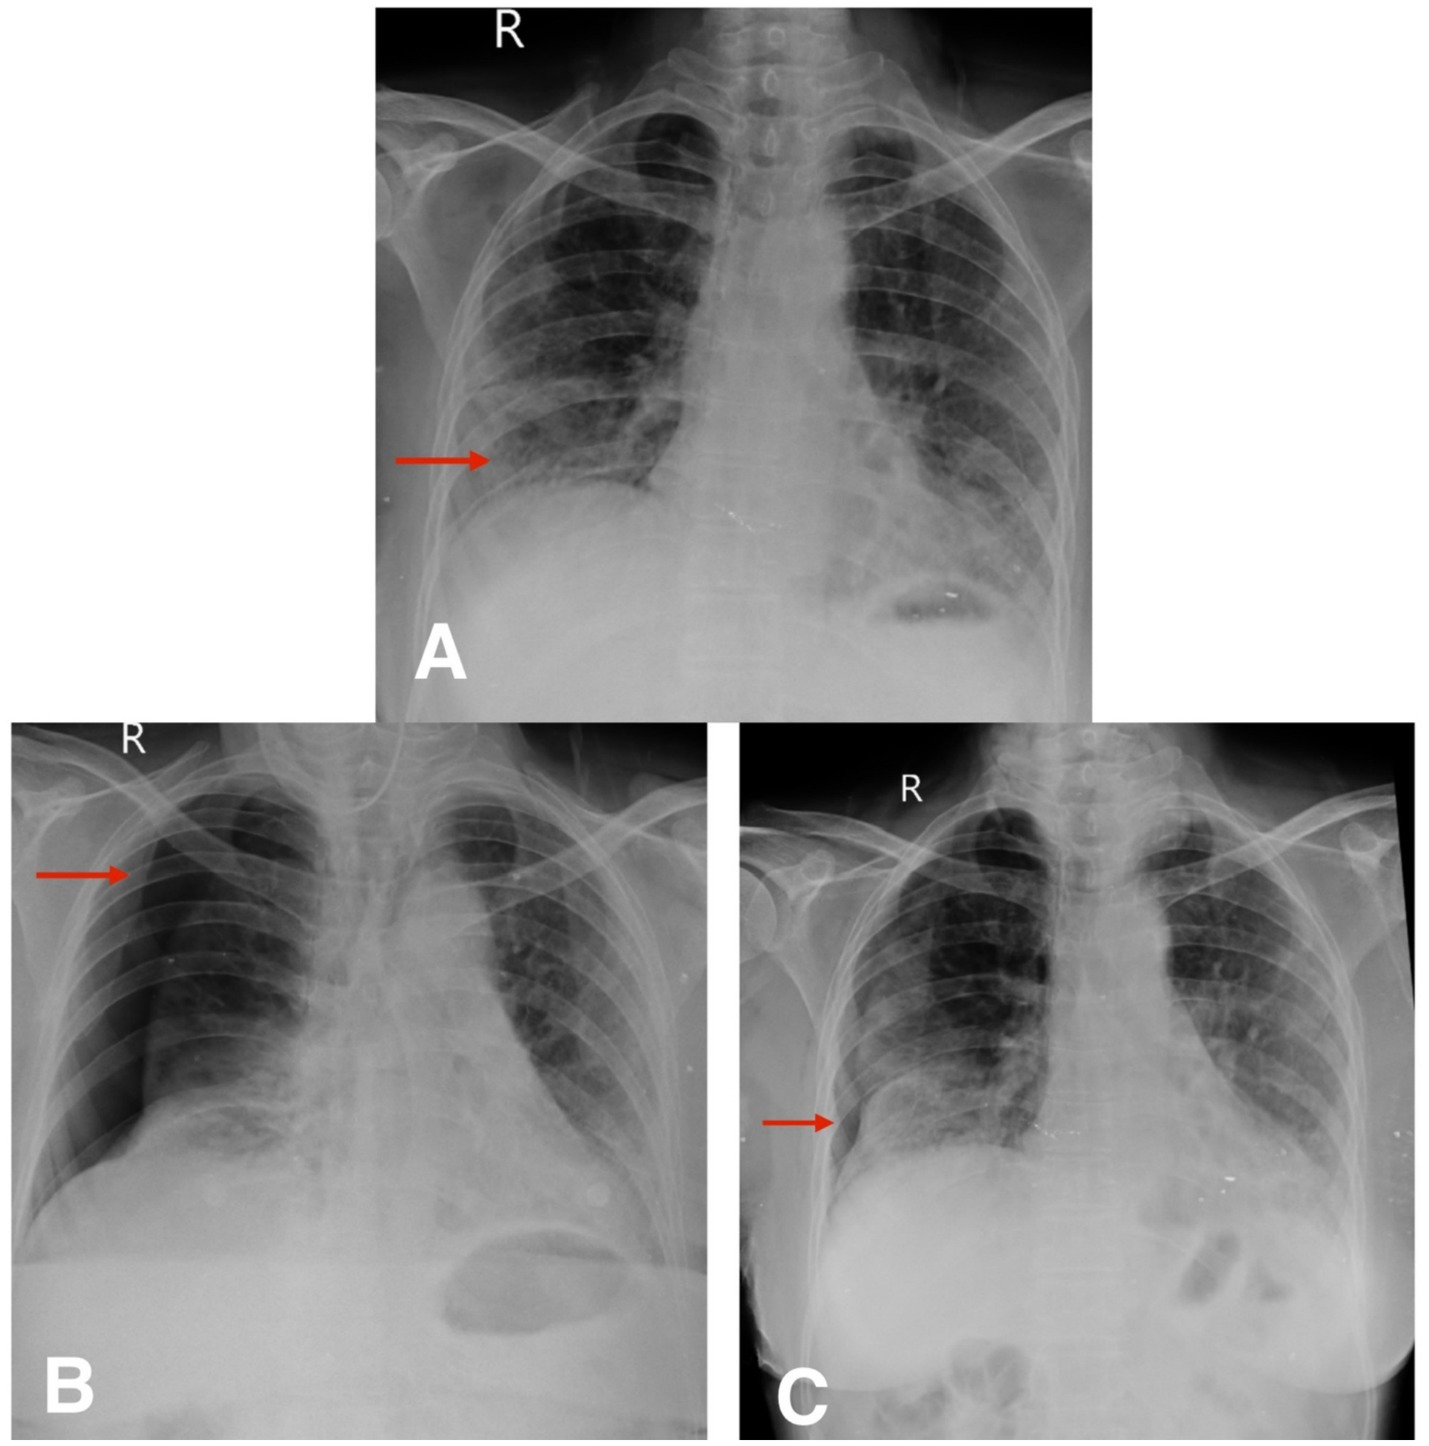

Radiological evaluation with chest X-ray showed reticular opacity in the right lower zone (Figure 4A), and HRCT thorax demonstrates extensive subpleural and basal reticular opacities, peripheral traction bronchiectasis, and a crazy paving pattern, consistent with a probable usual interstitial pneumonia (UIP) pattern (Figures 5A,B).

Figure 4. (A) Chest X-ray postero-anterior view shows reticular opacity in the right lower zone (red arrow). (B,C) Follow-up chest X-ray postero-anterior view shows spontaneous pneumothorax and slow resolution of pneumothorax (red arrow).

The second patient was hospitalized for 8 days during her initial presentation and treatment. Following discharge, she returned for a scheduled outpatient evaluation 2 weeks later. At this visit, she reported increased shortness of breath and chest discomfort. On presentation, her SpO₂ was 91% on room air. Supplemental oxygen was administered via nasal prongs at a flow rate of 4 L/min, titrated to maintain oxygen saturation above 94%. She remained hemodynamically stable throughout follow-up and did not require escalation to non-invasive or high-flow support. Chest X-ray confirmed the presence of a spontaneous pneumothorax (Figure 4B). Given her stable vitals and adequate oxygen saturation, she was managed conservatively with observation, supplemental oxygen, and supportive care. Follow-up chest X-rays over the next 2 weeks demonstrated gradual re-expansion of the lung (Figure 4C), and resolution of the pneumothorax was confirmed on high-resolution computed tomography (HRCT) (Figures 5C,D). The patient continues to be monitored at monthly intervals through outpatient visits, with adherence to antifibrotic and supportive therapy.